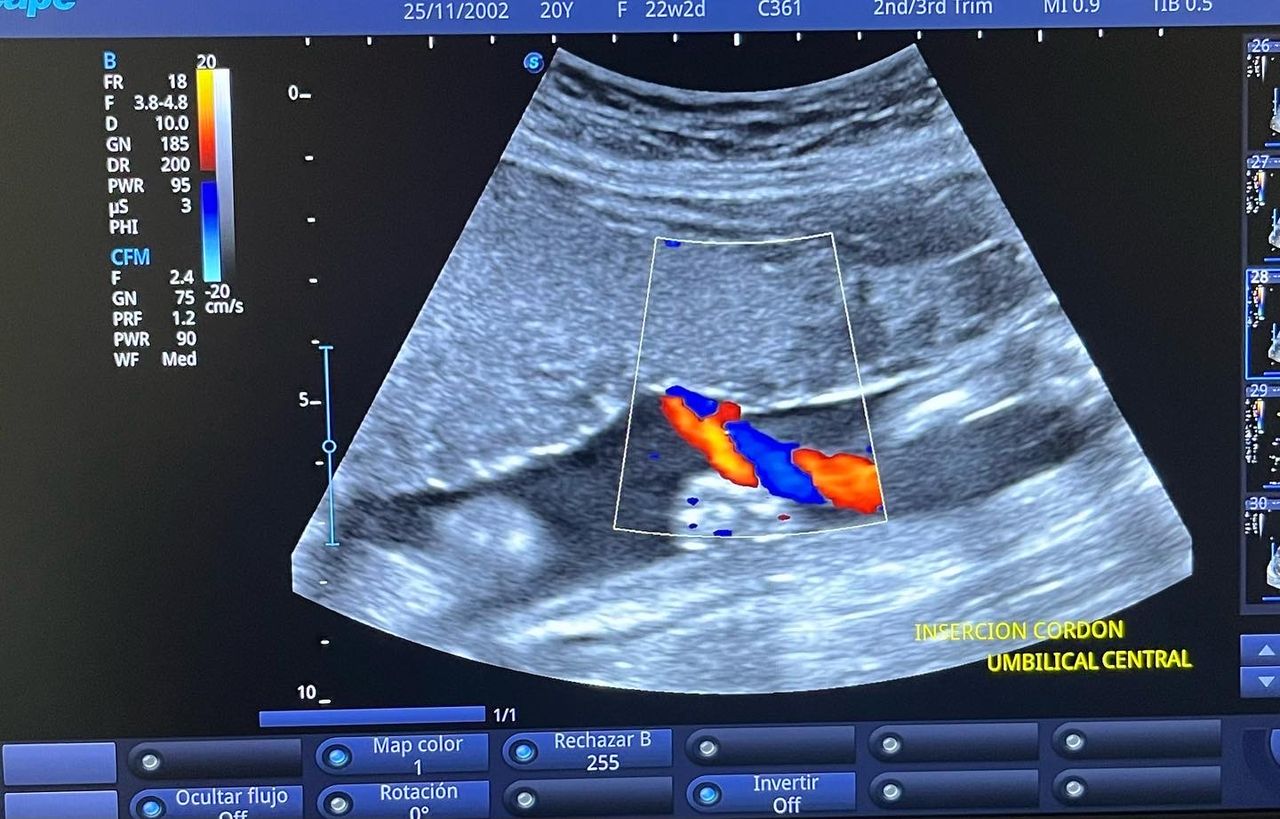

Médico general con 15 años de experiencia, master en enfermedades infecciosas y antibioticoterapia por parte de la Universidad Cardenal Herrera en Valencia, ademas de diversos diplomados en el área de Infectología y Parasitología, Urgencias, Imagenología y Medicina del Trabajo. He laborado en Hospitales y Clínicas en el área de Urgencias, en Laboratorios realizando estudios de Imagen, en especifico ultrasonidos de todo tipo desde básicos hasta avanzados incluidos los obstétricos estructurales, en Secretaría de Salud del Estado de Querétaro realizando ultrasonidos obstétricos para la detección de malformaciones en los tres trimestres del embarazo en diversos centros de salud, como médico de Empresas en el campo de Salud Laboral y actualmente en este consultorio en donde para su mejor atención y siempre buscando integrar la mayoría de las herramientas diagnosticas cuento con equipo de ultrasonido como apoyo en la exploración del paciente o como servicio diagnostico por imagen, realizo ultrasonidos convencionales (hepatobiliar (hígado, páncreas, vesícula y bazo), vías urinarias, ginecológico abdominal y transvaginal, tiroideo, prostático, testicular, pared abdominal) y especializados (dopler obstétrico en los 3 trimestres de embarazo), musculoesquelético en lesiones deportivas. También cuento con un equipo de electrocardiograma de 12 derivaciones para monitoreo completo del funcionamiento cardiaco, espirometria para evaluar la función pulmonar en la consulta, pruebas rápidas que se realizan en consultorio para detectar de forma mas precisa enfermedades infecciosas como Influenza A y B, covid19, infecciones urinarias, dengue, zika, chikungunya. Cuento con diversas vacunas para prevención de enfermedades. Siempre con el objetivo de dar el mejor servicio y atención a su salud. Lo espero en consulta para escucharlo y estudiar su caso de la forma más completa posible, estoy seguro de que tendremos las mejores opciones para su tratamiento. Mi tranquilidad es que usted se vaya con todas sus preguntas e inquietudes resueltas.

• Ultrasonido obstétrico